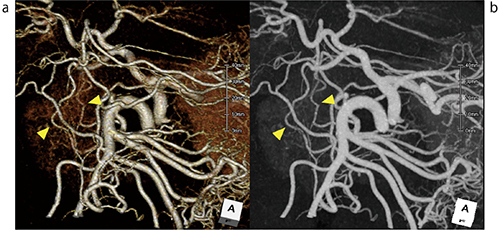

図1 化学療法前後の同一症例

a:化学療法前:通常のCTA、b:化学療法後:ニトログリセリンを使用したCTA

ニトログリセリンを用いることによって、通常のCTAでは描出できていなかった

腹部末梢血管の描出能が向上している。